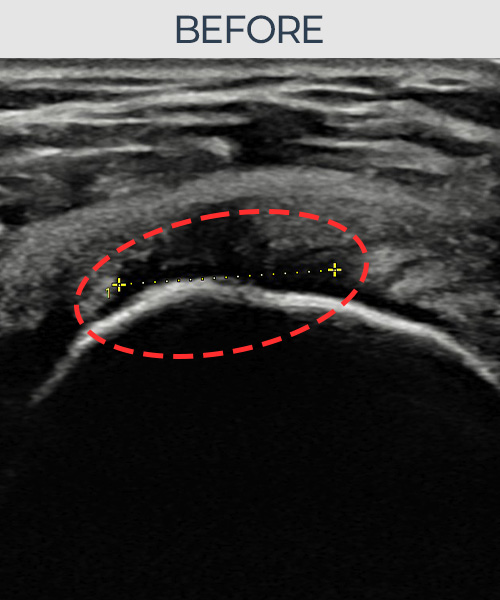

비수술 치료 전후사진

인대강화 주사가 아닌

인대재생 주사!

비수술로도 파열된 인대를

물리적으로 재건해 드립니다

플래티넘정형외과에서는 수술없이도 물리적으로

파열된 인대를 재건

하는것이 가능합니다.